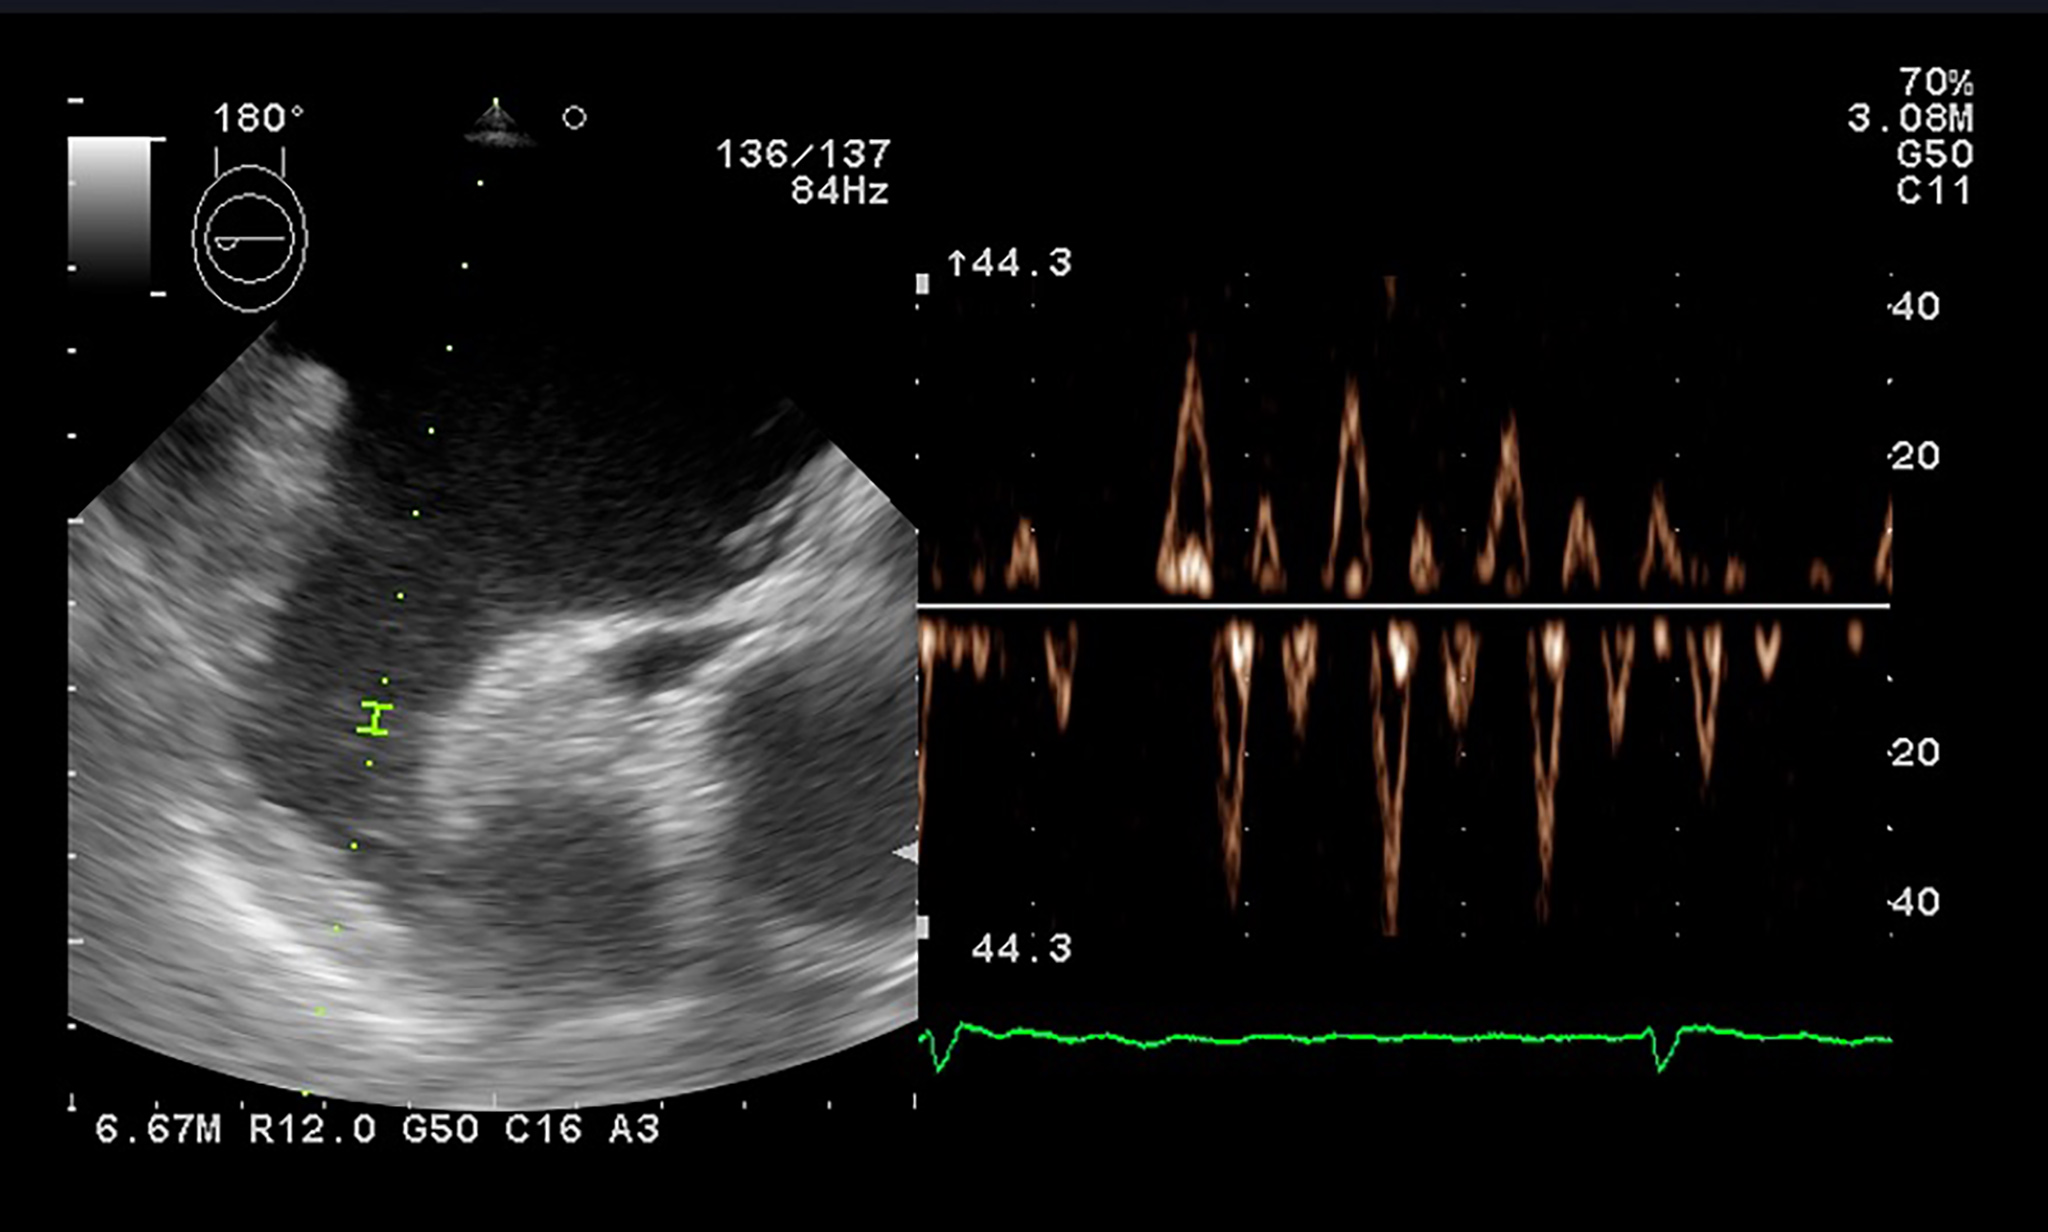

PW tissue Doppler imaging (TDI) is performed in the apical 4-chamber view, with the sample volume placed at the level of the mitral annulus, to evaluate the left ventricular wall motion (Fig. 7). The E/E’ ratio, correlates to LA pressures and is associated with an increased risk of late AF recurrence after catheter ablation. The risk is 3.32 times higher for a threshold over 13.25 [75].

Fig. 7.

Fig. 7.PW Tissue Doppler evaluation at the level of the septal mitral annulus for evaluation of E’ and A’.

TDI can also assess an atrial segment of interest, and measurements are usually done at the lateral wall level. The peak velocity in late diastole correlates to atrial contraction (A’) and is a rapid and accurate marker of atrial function. Hesse et al. [76] demonstrated a good correlation between A’ and LA fractional area and volume change in quantifying LA systolic function.

In AF patients there is a decreased compliance of LA walls, as during AF the reservoir and conduit function are impaired, and the booster pump function is lost. The S wave corresponds to the reservoir function, the lateral atrial E’ wave to the blood conduit, and the atrial A’ wave to the atrial contraction function.

The LA activity closely relies on the left ventricle functional parameters, and changes in left ventricle function and left atrial mechanics are independent and interrelated. Diastolic dysfunction and AF have many common risk factors, including aging [77]. It is known that most diastolic parameters vary with age: E and E’ wave velocities decrease, while the A wave, the E wave deceleration time and E/E’ ratio increase depending on age [78].

Not only the presence, but also the severity of left ventricle diastolic dysfunction is independently predictive of newly developed AF [79]. Early diastole filling evaluated by tissue Doppler mitral annulus motion velocity (the E’ wave) is reduced in patients with diastolic impairment. In this context, the E/E’ ratio evaluates filling pressures of the LA and left ventricle stiffness. In patients with diastolic dysfunction, the E/E’ ratio is used as an independent predictor of AF [80]. The relationship between transmitral E velocity (related to LA pressure and left ventricle relaxation) and tissue Doppler mitral annulus velocity (E’ – reflects left ventricle relaxation) reflects atrial pressures, irrespective of left ventricular function. This ratio seems to have a clinical relevance in risk stratification in patients with AF. A ratio over 11.2 was determined as a predictor for early AF recurrences [55], while a higher ratio, over 13.25, was established as an independent predictor for late AF recurrences [75]. A septal E/E’ ratio over 15 was evaluated as an independent predictor of mortality in patients with AF [81]. Both lateral atrial E’ and the ratio E’/A’ show a good correlation with various diastolic dysfunction parameters and LA strain [82]. While E/E’ ratio has been validated as an independent predictor of evolution and recurrences in the evaluation of outcome in patients with AF, data regarding thresholds are still missing [37, 55].

Atrial electromechanical delay or LA dyssynchrony time can also be measured by TDI. It is a feasible method that can evaluate the presence and extent of LA remodeling in addition to conventional echocardiographic parameters. TDI PA peak time (PA peak - TDI) is defined as the time measured from the start of the P wave in lead II to the peak of A wave on the tissue Doppler tracing from the lateral LA wall. Left atrial asynchrony was demonstrated to be an independent predictor for AF recurrence after radiofrequency ablation [83].

Tissue imaging is mostly used in clinical practice to determine the E/E’ ratio, as this parameter gives information about the relation between the LA and the left ventricle.